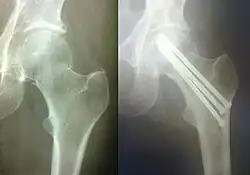

Остеоси́нтез (др.-греч. ὀστέον — кость; σύνθεσις — сочленение, соединение) — хирургическая репозиция костных отломков при помощи различных фиксирующих конструкций, обеспечивающих длительное устранение их подвижности. Цель остеосинтеза — обеспечение стабильной фиксации отломков в правильном положении с сохранением функциональной оси сегмента, стабилизация зоны перелома до полного сращения.

Погружной остеосинтез — это оперативное введение фиксатора кости непосредственно в зону перелома. В зависимости от расположения фиксатора по отношению к кости данный метод бывает внутрикостным (интрамедуллярным), накостным и чрескостным. Для внутрикостного остеосинтеза используют различные виды стержней (гвозди, штифты), для накостного — различные пластинки с винтами, шурупами, для чрескостного — винты, спицы. Нередко возможно сочетание этих видов остеосинтеза.

Накостный (экстрамедулярный) остеосинтез производят с помощью фиксаторов-пластин различной толщины и формы, соединяемых с костью при помощи шурупов и винтов. Иногда при накостном остеосинтезе в качестве фиксаторов возможно применение металлической проволоки, лент, колец и полуколец, крайне редко — мягкого шовного материала (лавсана, шёлка).

При чрескостном остеосинтезе фиксаторы проводятся в поперечном или косопоперечном направлении через стенки костной трубки в зоне перелома.